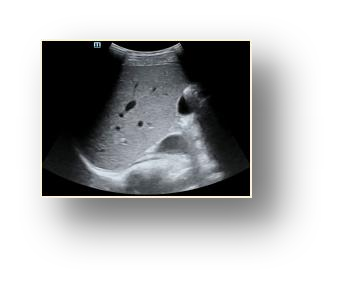

Most deep neural networks (DNNs) based ultrasound (US) medical image analysis models use pretrained backbones (e.g., ImageNet) for better model generalization. However, the domain gap between natural and medical images causes an inevitable performance bottleneck. To alleviate this problem, an US dataset named US-4 is constructed for direct pretraining on the same domain. It contains over 23,000 images from four US video sub-datasets. To learn robust features from US-4, we propose an US semi-supervised contrastive learning method, named USCL, for pretraining. In order to avoid high similarities between negative pairs as well as mine abundant visual features from limited US videos, USCL adopts a sample pair generation method to enrich the feature involved in a single step of contrastive optimization. Extensive experiments on several downstream tasks show the superiority of USCL pretraining against ImageNet pretraining and other state-of-the-art (SOTA) pretraining approaches. In particular, USCL pretrained backbone achieves fine-tuning accuracy of over 94% on POCUS dataset, which is 10% higher than 84% of the ImageNet pretrained model. The source codes of this work are available at https://github.com/983632847/USCL.